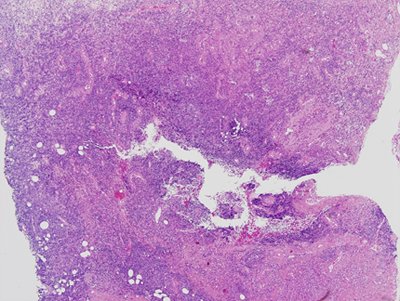

La lesión cutánea fue biopsiada. La biopsia reveló un denso infiltrado perivascular y perianexal compuesto de neutrófilos, linfocitos pequeños e histiocitos en toda la dermis, alcanzando la grasa subcutánea (Figura 1) con tejido de granulación y abscesos subcutáneos. Además se observaron agregados de linfocitos pequeños con contornos irregulares de cromatina nuclear y agrupada, infiltrando las lesiones de hidrosadenitis supurativa. (Figura 2).

Figura 1: linfocitos en dermis y tejido celular subcutáneo